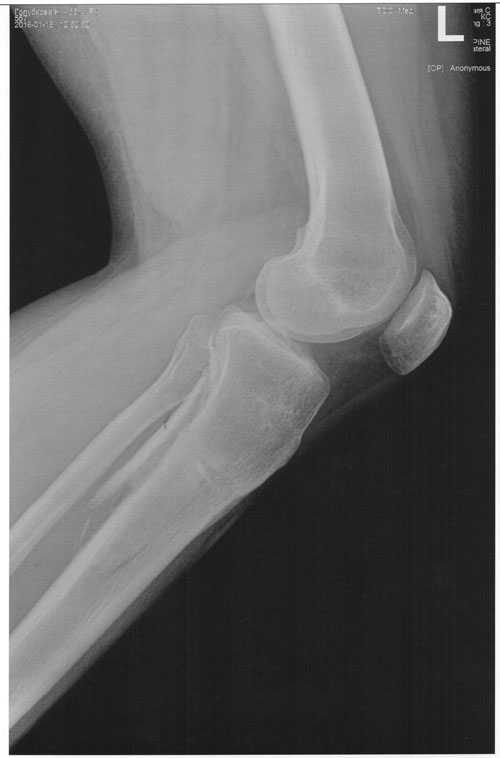

Исходник.

РЕНТГЕН ДО ОПЕРАЦИИ